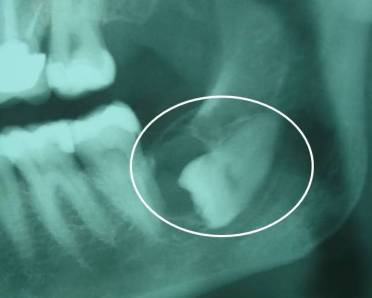

1- DENTES RETIDOS OU INCLUSOS (DENTES DO SISO)

Remover dentes retidos ou dentes do siso é uma cirurgia que eu faço quase que diariamente com enorme prazer e satisfação.